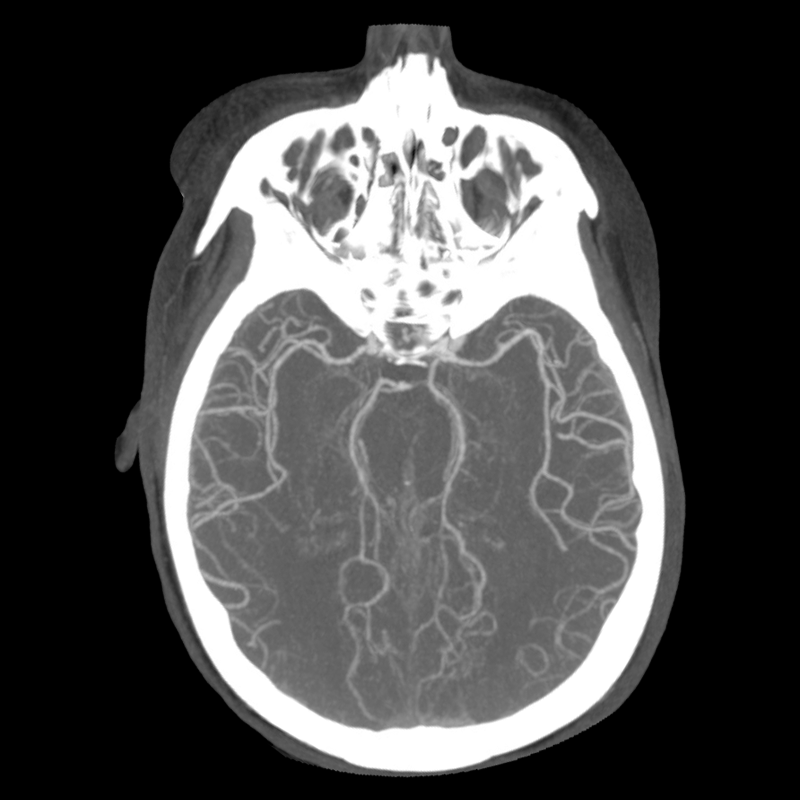

You arrive at the patient's room. You quickly examine her. Her left pupil is truly dilated and unreactive. Her right pupil is also dilated and unreactive, and also deviates to the right. She is unable to follow commands but is moving her extremities spontaneously. The right side of her body seems to be moving slightly less than her left. You escort the patient with RRT and your neurology colleague to radiology, where a non-contrast head CT and CTA head/neck are obtained.

CTA part 1 CTA part 2 CTA part 3

The non-contrast head CT looks generally similar to her prior scan. There's no new hemorrhage anywhere. There's no mass effect causing midbrain compression. The vessel imaging also looks unrevealing-- a slightly hypoplastic right A1 segment, but no clear LVO in either the anterior or posterior circulation. There's no vasoconstriction.